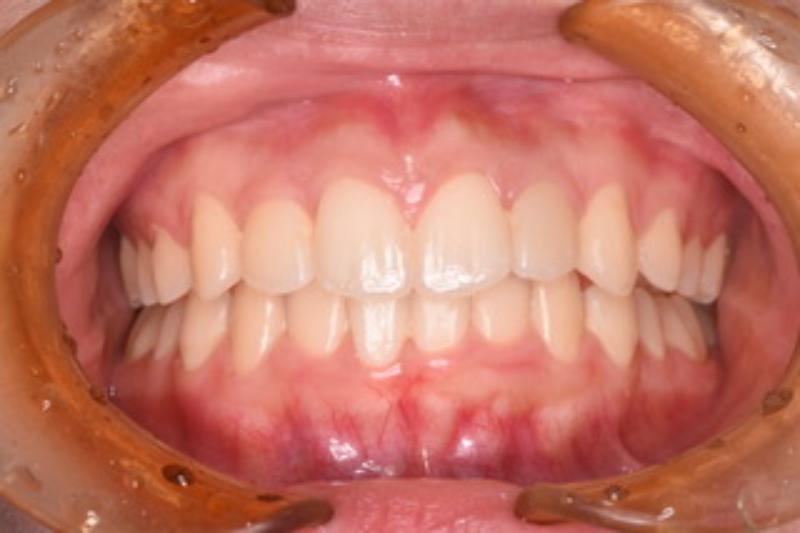

【術前】 【術中】 【術後】

前歯のガタつきと口元を引っ込めたい(口ゴボ)のため受診された16歳女性の方は、下顎前歯部のガタつきと、上顎の狭窄及び下顎の後退が予測されました。上顎の前歯をマウスピース矯正で引き込むだけでなく下顎を正常な位置まで戻すことで噛み合わせを再構築し、前歯のガタつきを抜歯する事なく改善できたそうです。

【治療部位】上顎・下顎

【治療期間】36ヶ月間

【治療回数】30回

【リスク】矯正しても横顔(口ゴボ)が改善しない事がある

【治療費用】精密検査:50,000円(税込)

一時矯正:900,000円(税込)

調整:0 円

合計:950,000円(税込)